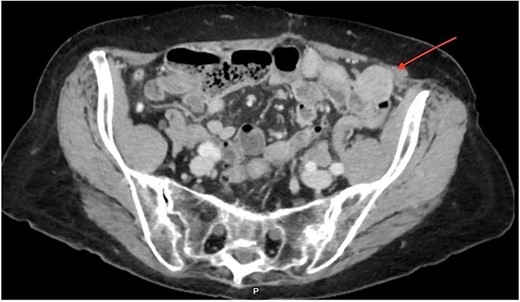

An 84-year-old female with an R0 oncologic hepatic resection for HCC 11 years ago presented with high alpha-fetoprotein (AFP) levels, followed by a computed tomography (CT) scan revealing a pelvic mass. After her index hepatic resection, she was managed with serial imaging and AFP tumor marker levels. The most recent AFP was elevated at 20.4 ng/ml, up from a previous value of 1.5 ng/ml one year earlier (normal range < 6.1 ng/ml). The CT demonstrated a 2.7 cm heterogeneous mass in the left lower quadrant, which was suspicious for a neoplasm. (Figs 1 and 2) The patient denied having abdominal symptoms, and the mass was not palpable during the physical exam.

CT imaging of the pelvis (axial section) displaying a rounded 2.7 × 2.7 cm heterogeneous mass localized in the left anterior pelvic cavity, near the colon wall, without peripheral enhancement.